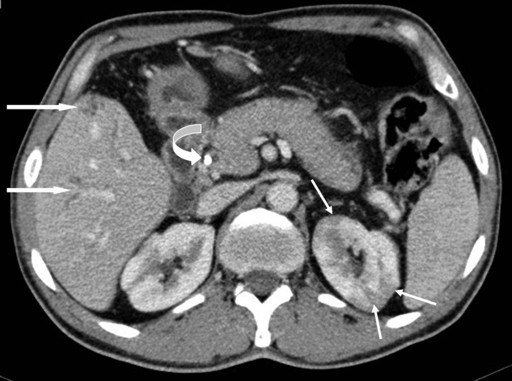

The most common findings on imaging were bulky pancreas with loss of lobulations and common bile duct stricture, and the majority (4/5) underwent common bile duct stenting (Figures 2 and 3). IgG4 serology was carried out in 4 of the 5 patients and it was positive in 3 of them. Two of the patients had extrapancreatic manifestations in the form of hypodense lesions in the kidney (2/5) and mediastinal lymphadenopathy (1/5). All patients were treated with prednisolone 40 mg/day for 4 weeks followed by a tapering off of 5 mg per week over the next 7 weeks; all of them showed rapid clinical improvement. Follow-up liver function tests showed resolution of hyperbilirubinemia and a decrease in serum alkaline phosphatase. Patients with common bile duct stricture underwent repeat ERCP and their cholangiograms showed resolution of the stricture following therapy with steroids (Figure 3). There was no recurrence after a follow-up of 6-8 months.

Figure 2. Contrast-enhanced computed tomographic axial image shows a diffusely enlarged pancreas with loss of lobulations. There are multiple hypoattenuating lesions seen in the left kidney (thin arrows). Note dilated intrahepatic biliary radicals (thick arrows) and plastic common bile duct stent in-situ (curved arrow). |

Imaging findings suggestive of autoimmune pancreatitis are the presence of focal or diffuse enlargement of the gland (sausage-shaped) with loss of lobulations with or without a capsule-like rim and the absence of vascular encasement or calcification [23, 24, 25]. Extrapancreatic manifestations are quite common in autoimmune pancreatitis and, if present, can aid in strengthening the diagnosis. The biliary tract is the most common extrapancreatic system to be involved in autoimmune pancreatitis (30-90%). Both intrahepatic and extrahepatic bile ducts can be affected; however, the distal common bile duct is the most common site of involvement [23, 24, 25]. Renal involvement is also common (35%) in the form of multiple small hypoattenuating peripheral cortical rounded wedge-shaped nodules [26]. Other extrapancreatic manifestations in autoimmune pancreatitis include hilar lymphadenopathy, lacrimal and salivary gland involvement and retroperitoneal fibrosis [24, 25]. The hallmark finding on ERCP in patients with autoimmune pancreatitis is a focal, diffuse or segmental attenuation of the main pancreatic duct and the disappearance of right-angled branches. The main pancreatic duct adjacent to or upstream of the strictures is minimally dilated. Other common findings on ERCP are the narrowing of the intrapancreatic portion of the common bile duct, irregular narrowing of the extrahepatic bile ducts and, less frequently, enlarged intrahepatic bile ducts [25, 27]. Pancreatographic findings were available in 3 of our patients and they all showed uneven contour and dilatation of the main pancreatic duct.